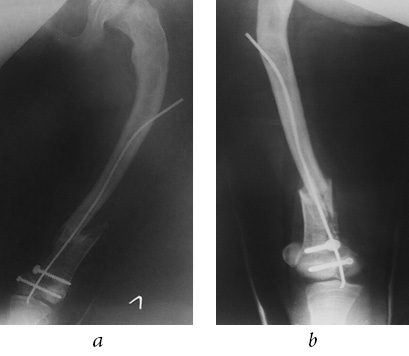

According to the radiographs performed in a primary care facility (of poor quality, in one projection), a closed, comminuted intra-articular fracture of the distal metaepiphysis of left femur (Salter-Harris IV) was diagnosed with a transition to the shaft with the displacement of fragments (Fig. 2); in addition, a closed fracture of the right femoral bone in the lower third of the shaft with mild displacement of fragments was observed (Fig. 3). TEN in the intramedullary canal of right femur prevented a severe displacement of the fragments. As a result of the fracture, TEN was deformed.

Fig. 2. Intraoperative radiographs of the left femur: a — frontal view; b — lateral view

Fig. 3. Intraoperative radiographs of the right femur: a — frontal view; b — lateral view